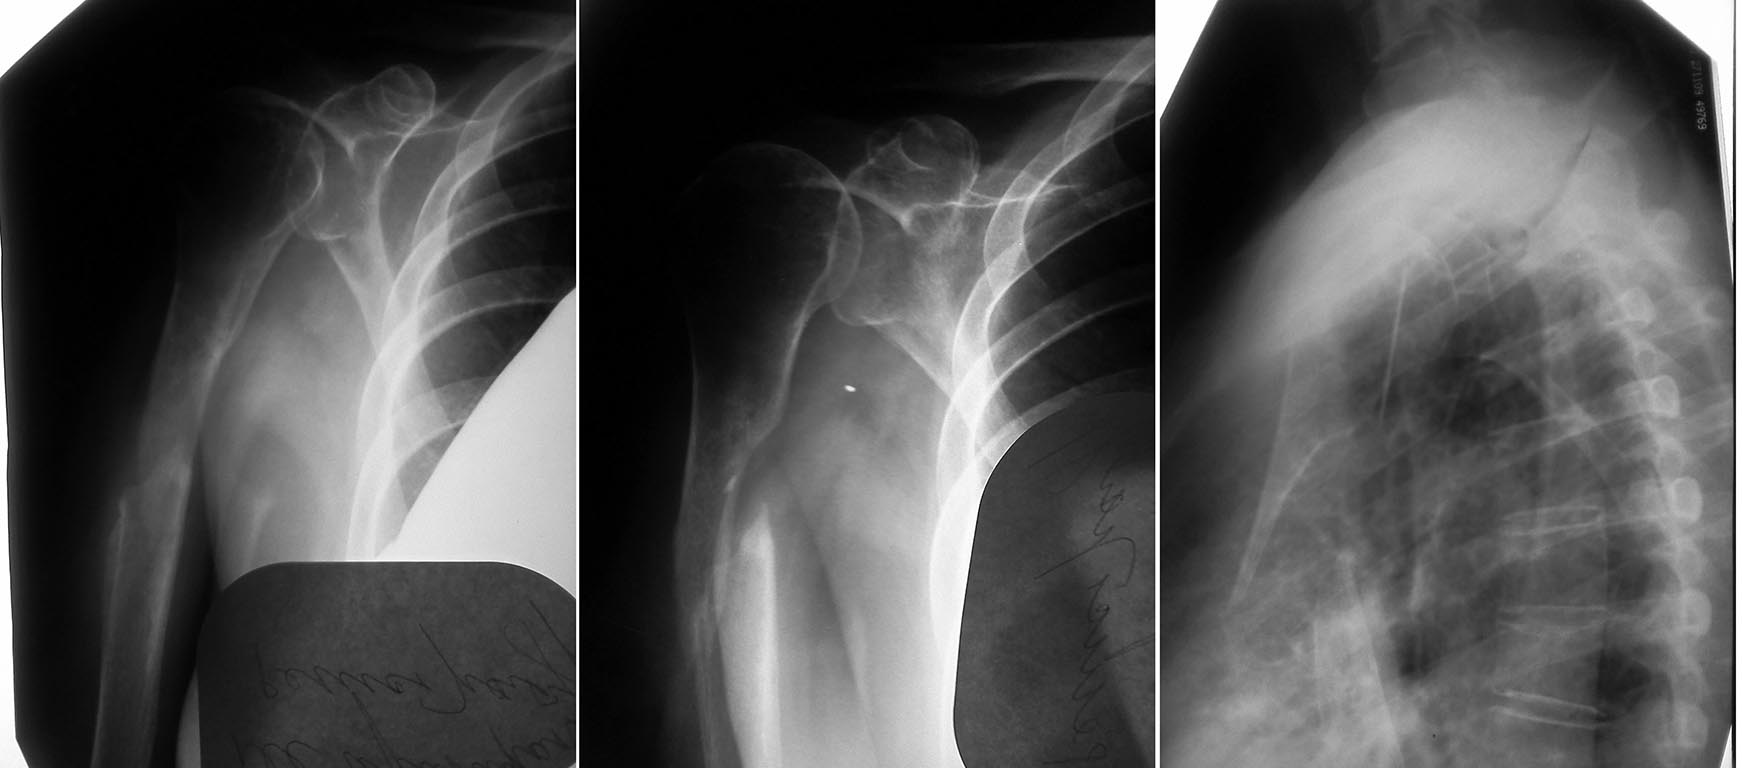

Всем доброго времени суток! В отделение поступила пациентка О. 54 лет. В

анамнезе в июле 2011 года перелом верхней трети диафиза правой плечевой

кости.

Лечилась консервативно. Гипсовая иммобилизация 6 недель. Результат не

был достигнут. К врачам не ходила. На данный момент имеется следующая

рентгенологическая картина. Да...... Какие есть варианты по лечению?

Остеосинтез пластиной....Укорочение...или в данном случае можно

рассмотреть вариант с костной пластикой. Прошу высказать Ваши мысли по

данному случаю. Спасибо всем откликнувшимся.